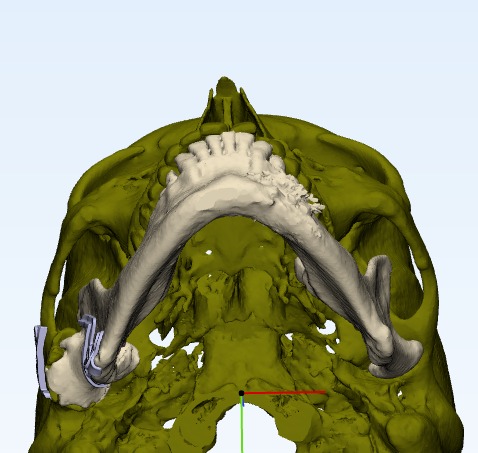

Tmj anklosys leading to deficient mandible and deficient chin corrected by TMJ Surgery followed by Orthognathic surgery